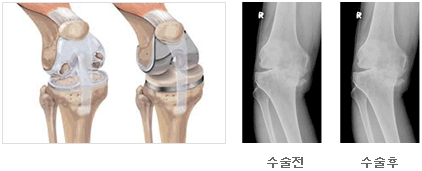

무릎관절의 외상이나 질환으로 통증, 운동장애, 변형 등 보행장애가 있을때 변형된 무릎 관절부위를 제거하고 인공으로 된 관절면으로 바꾸어주는 수술을 말한다. 무릎 관절의 인공 관절은 관절 내 연골이 닳아서 뼈와 뼈가 맞닿아 생기는 심한 통증 때문에 도저히 일상 생활이 되지 않는 경우나 통증이나 구축등으로 무릎관절의 운동에 심한 제한이 있을 때 일차적인 대상이 된다. 원인이 되는 질환으로는 중등도 이상의 퇴행성 관절염이 가장 흔하며 그 외 심한 관절의 파괴를 동반한 류마티스성 관절염, 기타원인으로 인한 관절염(감염,외상) 등이다. 그러나 상기 질환이 있더라도 엉덩이 인공 관절과 마찬가지로 모두 인공 관절을 해야 하는 것은 아니다. 어느 정도의 관절에 문제가 있더라도 심한 통증이나 관절운동의 제한이 없는 경우에는 인공 관절 시술을 받을 필요가 없고 수술 시기도 가능한 한 젊은 나이를 피하는 게 좋다.